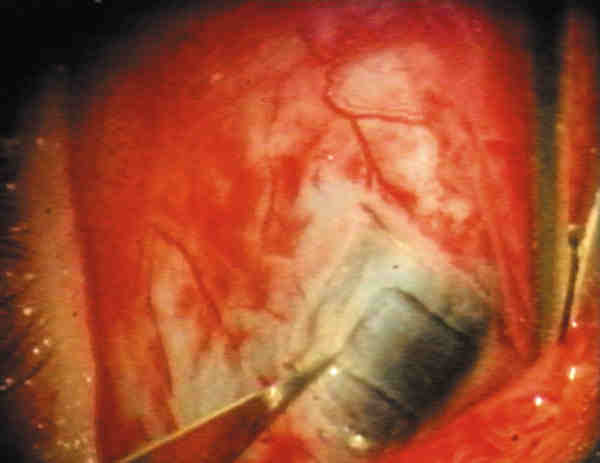

10. Iridectomía (figura 5): Debe ser más amplia que la apertura de la trabeculectomía, con el fin de impedir la incarceración iridiana. Para ello se prende el iris cerca de su raíz con una pinza dentada y se secciona con una tijera de Vannas sostenida en sentido circunferencial. En el primer movimiento para un cirujano diestro, la pinza desplaza el iris hacia la izquierda mientras la tijera secciona la mitad del tejido. En el segundo tiempo, la pinza desplaza el iris hacia la derecha mientras tracciona levemente de él y se concluye la iridectomía.

08-05.jpg (11319 bytes)

Figura 5. Iridectomía.